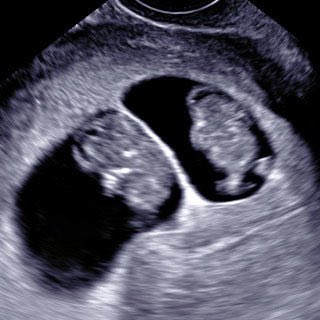

٧- في يوم ترجيع الاجنة (الخامس) يتم تحديد افضل الاجنة الصالحة للترجيع وغالبا (٢) ويتم ارجاعها لتجويف الرحم ويطلب من الزوجة ان تكون المثانة شبه ممتلئة لتسهيل مرور قسطرة ترجيع الاجنة للرحم بسهولة ويستغرق دقائق فقط...

٩- بعد اسبوعين من ترجيع الاجنة يتم عمل تحليل الدم الرقمي لمعرفة حدوث الحمل واذا كان ايجابيا يتم تكراره مرتين لمعرفة ارتفاع مستواه وبعد أسبوعين من التحليل الايجابي أي ٤ أسابيع من تاريخ إرجاع الأجنة يتم عمل الاشعة الصوتية لمعرفة مكان الحمل وعدد اكياس الحمل ونبض الجنين..